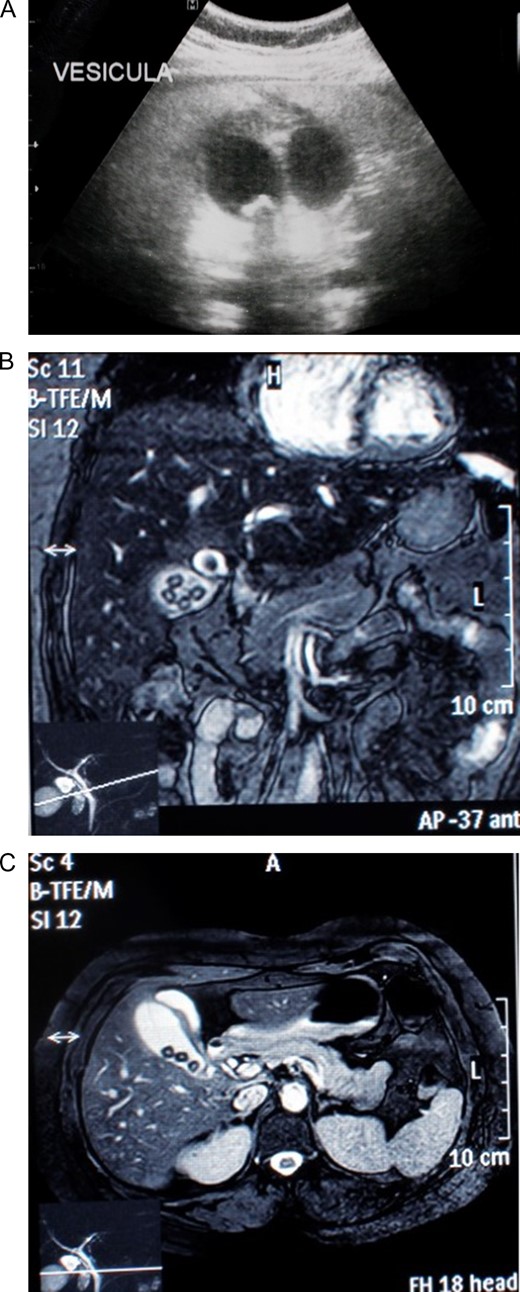

At laparoscopy, multiple adhesions from omentum to the gallbladder fossa were seen and released, revealing the Calot’s triangle structures. After achieving critical view of safety, a gallbladder duplication was identified, the right gallbladder had purulent bile with thickening of its walls, the second gallbladder appeared normal. Both of them had independent cystic ducts, but only one cystic artery was detected (Fig. 2A and Supplementary Video). From there surgery was straightforward, clips were applied to the common cystic duct and cystic artery respectively and they were divided between the clips without any complications. After that, the gallbladders were dissected off the gallbladder fossa using electrocautery and retrieved in a latex bag via the umbilical port.

(A) Laparoscopic view of two gallbladders, each with its’s individual cyst duct and an oedematous wall in one of them. (B) Gallbladder duplication with two independent cystic ducts. (C) Thickened muscular layer and vascular congestion of gallbladder wall.

Pathology reported two permeable cystic ducts, and two separated gallbladders divided by thick inflammatory tissue. Multiple 0.5 cm gallstones were discovered in the left gallbladder and biliary sludge in the right one (Fig. 2B). Microscopically, chronic exacerbated cholecystitis was detected in the right gallbladder (Fig. 2C). A Y-shaped gallbladder duplication with cholecystitis due to cholelithiasis in one of them was the final diagnosis